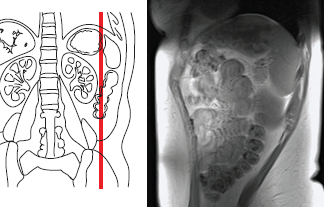

Магнитно-резонансная томография (МРТ) органов брюшной полости (печени, желчного пузыря, системы и поджелудочной железы) 3,0 Т (тесла) является методом выбора для дифференциальной диагностики образований паренхиматозных органов брюшной полости и забрюшинного пространства.

В настоящее время магнитно-резонансная томография (МРТ) органов брюшной полости (печени, желчного пузыря, системы и поджелудочной железы) 3,0 Т (тесла) является наиболее информативным методом в диагностике и дифференциальной диагностике очаговых поражений печени — метастазов, гемангиом, аденом, фокальной узловой гиперплазии, печеночно-клеточного рака и других опухолей и опухолевидных процессов.

Магнитно-резонансная томография (МРТ) органов брюшной полости 3,0 Т (тесла) хорошо выявляет плотные и кистозные опухоли поджелудочной железы.

Магнитно-резонансная томография (МРТ) почек и надпочечников 3,0 Т (тесла) показана:

- для уточнения характера объемного образования, выявленного с помощью других инструментальных методов исследования (дифференциация нормальных анатомических вариантов строения от патологических изменений, а также кист, от кистозных изменений при опухолевых процессах в почках);

Магнитно-резонансная томография (МРТ) почек и надпочечников 3,0 Т (тесла) является эффективным методом диагностики и позволяет с высокой точностью дифференцировать злокачественные и доброкачественные образования надпочечников с помощью специальных протоколов, высокочувствительных к наличию внутриклеточного жира в аденомах.